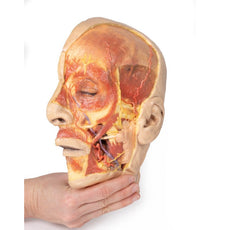

3D Printed Brain Hemisection

This 3D model is a midsagittal hemisection through a whole brain, preserving the right side anatomy and deep brain

structures and spaces visible in the midline. In lateral view, the right cerebral and cerebellar hemispheres are

covered in the arachnoid mater. In the midline view, the brain regions from the cerebrum to the medulla oblongata

are preserved. Centrally, the third ventricle is opened, with an intact septum pellucidum superiorly positioned and

obscuring the lateral ventricles within the cerebral hemisphere. On the inferior margin of the third ventricle both

the right mamillary body and right optic tract can be observed, whereas posteriorly the cerebral aqueduct can be

observed extending across the midbrain between the tectum and tegmentum towards the fourth ventricle (between the

cerebellum and pons). The cerebellum is separated from the occipital lobe by a preserved portion of the tentorium

cerebelli, and in cross-section the cerebellar cortex helps form the prominent arbor vitae.

A series of arterial

branches have been false coloured to contrast their course across the preserved brain structures. In the midsagittal

view the anterior cerebral artery courses from around the corpus callosum to supply the cingulate gyrus and other

midline cortical regions. The base of the middle cerebral artery can be seen passing deep between the temporal and

frontal lobes, with the posterior communicating artery connecting it to a small remnant of the posterior cerebral

artery. Adjacent to the posterior cerebral is the superior cerebellar artery, extending laterally to pass between

the temporal lobe and the cerebellum before passing deep into the transverse fissure.